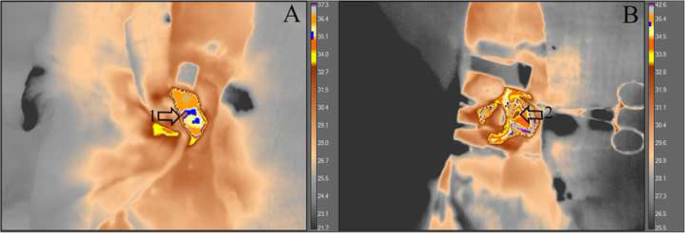

There was a reduction of heart temperature between the treated group and the sham group during M5 moment. This change can be visualized with green isotherm, indicating the myocardium temperature variation (sham group) (Fig. 5). Additionally, a temperature reduction of the myocardial tissue, was observed during the circulatory arrest period in the treated group (Fig. 6). The average temperature in the animals from the treated group during the experiment at moment 0 was approximately 35.1 °C - 36.4 °C and at moment 5 approximately 31.1 °C - 32.8 °C, representing temperature reduction of approximately 2.3 °C to 5.3 °C. While the untreated group had temperatures between 36.4 °C - 39 °C. Regarding hemogasometric evaluation, the following parameters were analyzed: pH, bicarbonate and PaCO2. The values obtained at moment M0 were considered as the control values in the treated group. The pH values significantly decreased during the ischemia and reperfusion periods, indicating the presence of acidosis (Fig. 7). The PaCO2 values increased during ischemia/reperfusion (Fig. 8). This result indicates that acidosis has a respiratory origin.

Videothermometry infrared during respiratory arrest and cardiac ischemia periods. The figure represents two groups; (a) sham group during ventilatory arrest period M5 and (b) treated group during cardiac ischemia period M5. Observe the respective temperature bars and the heat variations in the myocardial tissue according to the colors. In (a) a green isotherm was used and the temperature between 36.9 °C and 39 °C is noted. In (b) a blue isotherm was used and the temperature ranges between 32 °C and 34.5 °C. Arrows 1 and 2, indicate the location of the heart, in the caudal vena cava and right atrium areas, a brown spot is evident, meaning a cooler region with the temperature approximately 32 °C. The treated group, demonstrated a considerable reduction in temperature, indicating a significant decrease when myocardial ischemia occurs. UEA / UENF, 2015

Videothermometry infrared in a normal heart and in a ischemic heart. The images represent the treated group, at moments M0 (A) and M5 (B). In the moment 0 (a) note the blue isotherm, indicating a temperature approximately 35.1 °C and 36.4 °C (1). In the moment 5 (b) note the absence of the blue isotherm and the presence of colors which indicates a temperature between 31.1 °C and 32.8 °C (2). Through this sequence of images, it is possible to evaluate the temperature reduction that occurred between the beginning and the end of the procedure